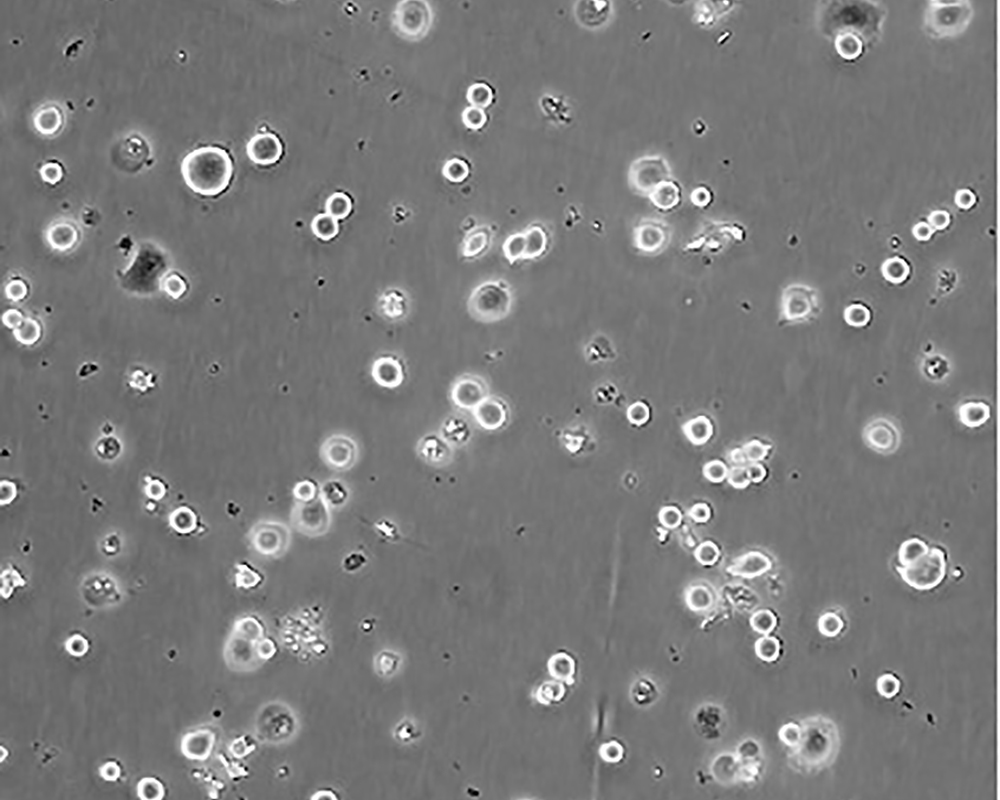

SK-BR-3 [SKBR-3;SKBR3]

產(chǎn)品名稱 SK-BR-3 [SKBR-3;SKBR3]

中文名稱 人乳腺腺癌細(xì)胞

組織來(lái)源 mammary gland/breast; derived from metastatic site: pleural effusion

生長(zhǎng)特性 adherent

形態(tài)特征 epithelial

細(xì)胞描述 he patient, a White, Caucasian female, age 43, blood type A+, had been treated with radiation, steroids, cytoxan and 5-fluorouracil.No virus particles.Ultrastructural features include microvilli and desmosomes, glycogen granules, large lysosomes, bundles of cytoplasmic fibrils.The SKBR- 3 cell line overexpresses the HER2/c-erb-2 gene product.